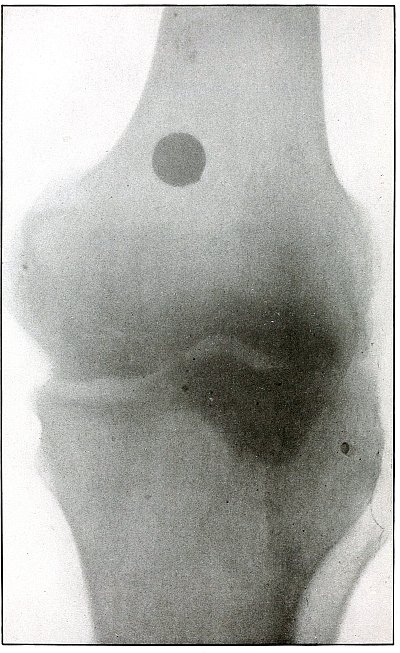

| 59. |

Gunshot wound, knee |

128 |